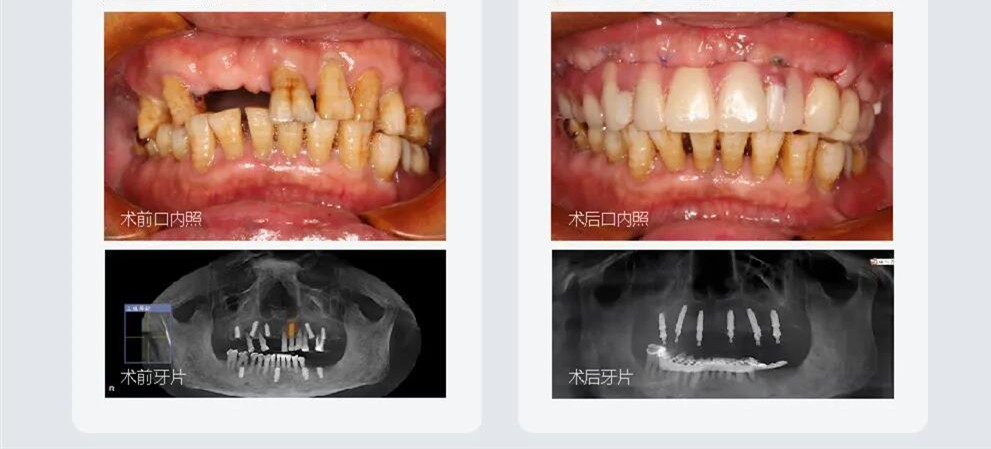

本院手術(shù)網(wǎng)友分享